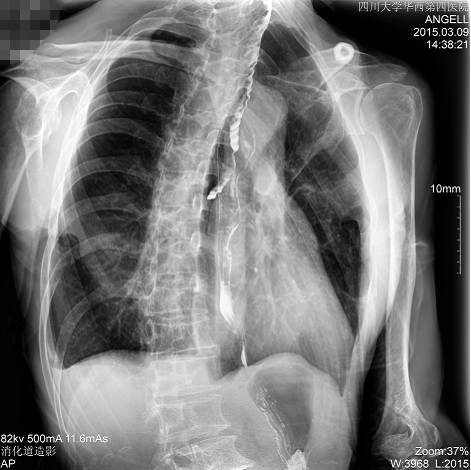

如下圖所示:該患者因吞咽時感到很難受,進(jìn)食時也經(jīng)常咳嗽故就醫(yī)診斷。使用多功能dr為病人進(jìn)行消化道造影診斷,要求他吞鋇后發(fā)現(xiàn),食道各段通過順利,形態(tài)規(guī)則,雙側(cè)梨狀窩不對稱左側(cè)稍淺,多次吞咽動作后,仍見鋇劑滯留,并見鋇劑進(jìn)入氣管,屬于會厭征陽性。會厭功能紊亂,鋇劑進(jìn)入了氣管。

圖為正位:通過動態(tài)影像可以清楚看到鋇劑進(jìn)入了支氣管道且雙側(cè)梨狀窩不對稱

通過多功能dr可以診斷該病人的癥狀為會厭功能紊亂,鋇劑進(jìn)入到了氣管。而在動態(tài)透視下可以清晰的觀察到鋇劑從何處進(jìn)入氣管,可清晰顯示食管粘膜結(jié)構(gòu)。使用多功能dr其獨特的視頻采集技術(shù),可實時保存視頻并能實現(xiàn)900萬像素實時點片,才能獲取這樣清晰的病灶點。而常規(guī)dr只能拍攝靜態(tài)片,且成像效果大打折扣,因此較難確診病灶。